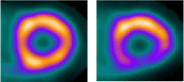

・負荷⼼筋⾎流シンチグラフィ

●PET/CT検査

⼀⽅、X線CT は⾝体の外からX線をあて、X線の影、すなわち臓器の「かたち」を画像化する検査です。PET/CT装置はPETとX線CTの複合機で、両者を組み合わせた情報が得られます。

●PET検査で何がわかりますか︖

●PET検査の有⽤性